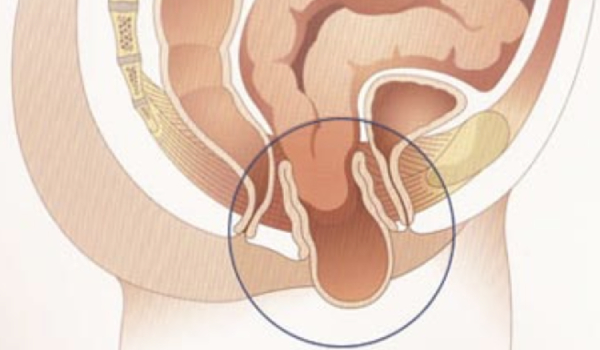

Reacomodación del recto en el interior del cuerpo.